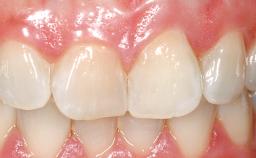

Immediate Placement of an Implant in a Maxillary Right Central Incisor Site

A 30-year-old female patient was referred to the office for the treatment of tooth 11. Her chief concern at the initial visit was to inquire, “Why is my tooth pink?” Upon clinical examination, it was determined that tooth 11 had a previous history of trauma and that the clinical crown had become noticeably pink in color as a result of internal resorption. This diagnosis was confirmed radiographically, indicating a large radiolucency involving the central and distal portions of the clinical crown. It was determined that restoration of this tooth was not possible, and that extraction was indicated. The presence of a mid-line diastema, which the patient wanted to reproduce, directed the treatment plan for tooth replacement utilizing a dental implant.

Prosthesis Type FDP

Mesio-Distal Space Asymmetry greater than 1 mm

Esthetic Risk High